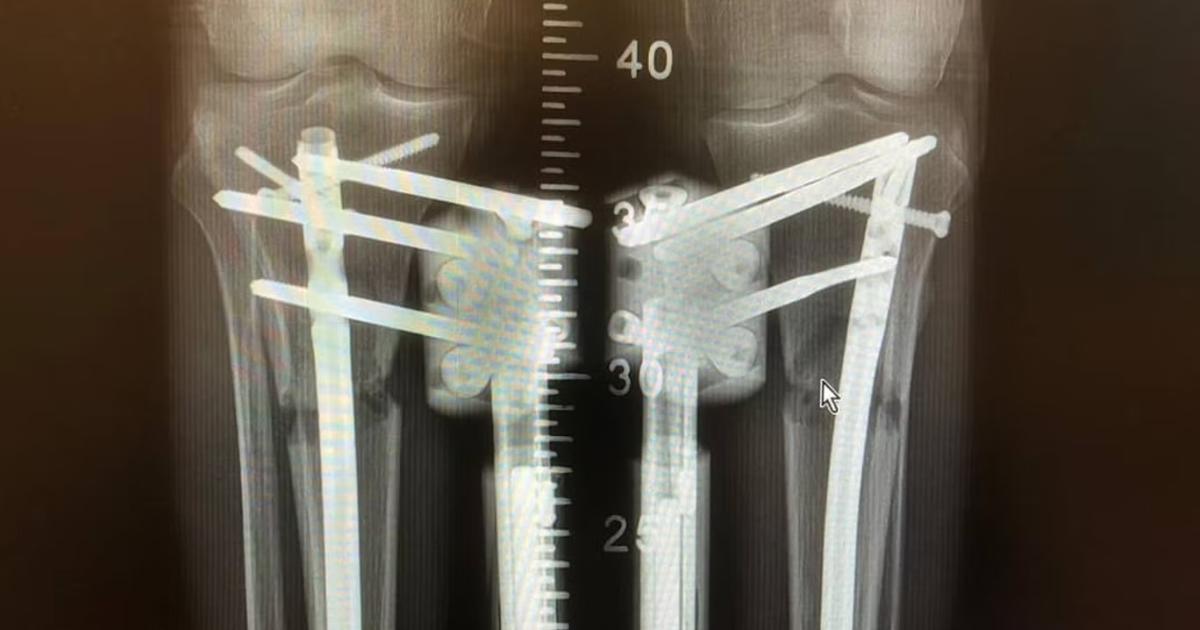

اس آپریشن کے بعد مکمل صحت یاب ہونے میں 80 دن سے زیادہ وقت لگتا ہے (Wanna Be Taller)

اس سے ران کی ہڈی میں ایک راستہ بنتا ہے جہاں ایک اندرونی لمبا کیل جڑ دیا جاتا ہے اور اسے پختہ کرنے کے لیے فریکچر کے اوپر اور نیچے ڈرل کر کے پیچ لگا دیے جاتے ہیں۔

پیچ کولہے سے ذرا نیچے اور گھٹنے سے اوپر ہوتے ہیں۔ سرجری کے بعد ریموٹ کنٹرول سے مقناطیسی سینسر چلائے جاتے ہیں تاکہ کیل کو تقریباً 1 ملی میٹر روزانہ کی رفتار سے بڑھایا جا سکے۔

جسم خالی جگہ کو پُر کرنے کے لیے نئی ہڈی پیدا کر کے اپنا ردعمل ظاہر کرتا ہے اور اس طرح تقریباً 80 دنوں کے عرصے میں فریکچر کے کنارے فاصلہ پاٹتے ہوئے نئی ہڈی کی صورت اختیار کر لیتے ہیں جس کی لمبائی عام طور پر دو سے تین انچ ہوتی ہے۔

ایل او این طریقہ اب بھی الیزاروف کی ایک تیکنیک  استعمال کرتا ہے، ایک قسم کا بیرونی فکسیٹر یا دھاتی فریم جو باہر سے ٹانگ کے گرد لپیٹا جاتا ہے اور پنیں لگا کر جلد کے ذریعے ہڈی سے منسلک کر دیا جاتا ہے۔

اس کے بعد ہوٹل میں دی جانی والی دیکھ بھال انتہائی اہمیت کی حامل ہے۔ جانا بتاتی ہیں کہ روزانہ کی سخت فزیوتھراپی اور سٹریچنگ ایکسرسائز کے ساتھ ساتھ  مریض کو ہر 15 دن میں ایکس رے کی ضرورت ہوتی ہے تاکہ یہ یقینی بنایا جا سکے کہ پہلے والی ہڈیاں نئی ہڈی بننے کی رفتار کی نسبت زیادہ تیزی سے الگ تو نہیں ہو رہیں۔